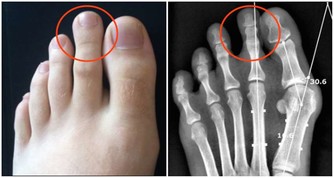

鼻咽癌晚期,殘酷的五個字,竟然和一名15歲少年聯系在了一起。由於發現晚,孩子也許只剩下5年時間…… 小明(化名)性格溫順,言語不多。父母在浙江打工,他跟著爺爺奶奶在老家安徽生活。3個月前,一直忙於農活的爺爺奶奶才注意到,孩子的脖子有些異常。 「脖子上就長了個包,有點硬,但是他身體都好好的, 我們也不知道呀。」現在回想起來,老人非常懊悔。由於缺乏醫學常識,小明脖子上的「包」越長越大,足足在脖子上突出了一個小拳頭大小,才告訴了父母。在當地醫院的檢查中,並沒有找到病因,後來父母把孩子接到杭州第一人民醫院,活檢證實是鼻咽癌。 「他這個年紀,怎麼會得癌症?」誰都不相信,尤其是小明的媽媽。 鼻咽癌在成人當中比較常見,兒童非常少見,但現在20、30歲的鼻咽癌患者在逐步增加,為什麼小明卻感染了呢? 影響因素一: 鼻咽癌的發病是多方面的原因,和EB病毒有關系,95%以上的成人都攜帶了這種病毒,它是傳染性單核細胞增多症的病原體,所以家長不要嘴對嘴的給孩子餵食物。 影響因素二: 鼻咽癌和生活習慣、外部環境都脫不了干係。喜歡吃醃漬的食物,比如鹹魚、臘腸、泡菜等,容易患上這種癌症。 【醃漬食品三大罪狀】 1.含有致癌物質——亞硝酸胺 醃漬食品在醃制過程中會產生亞硝胺前體物亞硝酸鹽。人的胃液pH值在1~3時,亞硝酸或硝酸鹽(需經細胞還原成亞硝酸鹽)可與細胞中的仲胺合成亞硝胺類化合物。這些物質有較強的致癌作用。 2.容易造成人體維生素C缺乏和結石 蔬菜在醃制過程中,維生素C被大量破壞。醃制後,維生素C的成分幾乎「全軍覆滅」。大量吃醃菜,人體維生素C缺乏。因此,適當吃點醃菜可以調節胃口,增加食慾,但若嗜食醃菜成癖,則是不可取的。如果長期食用,容易引起各種疾病。 另外,醃制的酸菜中含有較多的草酸和鈣,由於它酸度高,食用後不易在腸道內形成草酸鈣被排出體外,而會被大量吸收,草酸鈣就會結晶沉積在泌尿系統形成結石。 3.影響黏膜系統,對腸胃腎髒有害 由於食品在醃制過程中,需要大量放鹽,這會導致此類食物鈉鹽含量超標,造成常常進食醃制類食品者腎髒的負擔加重,發生高血壓的風險增高。 此外,高濃度的鹽分還會嚴重損害胃腸道黏膜,故常進食醃制類食品者,胃腸炎症和潰瘍的發病率較高。 如果一定要吃,也要在醃制15天後亞硝酸鹽下降至安全的劑量範圍內食用。 鼻咽癌早期有高達80%的治癒率,但是由於小明的情況比較特殊,家長反應慢,所以拖的時間較長,癌細胞已經轉移。「情況並不是特別樂觀。」李勇也表示惋惜,「治好了,可能也就5年時間吧。」 鼻咽癌的早期症狀 涕中帶血:早晨起床時,經常流鼻血,或是鼻涕呈淡粉色,有時帶血絲。 耳鳴,聽力減退,耳內閉塞感。頭痛:單側頑固性頭痛,偏頭痛多發生在顳頂部。頸部淋巴結腫大。鼻塞。 因為早期症狀不典型,多數被誤診為鼻炎,中耳炎,頸部淋巴結結核等。所以大家需要注意了,尤其是家長,如果一發現這些症狀,一定要及時就醫! 首頁還有更多熱門文章喔 網址傳送門 ww.happies.news